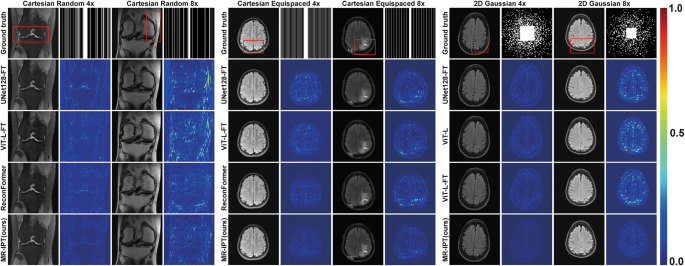

Figure 2 illustrates qualitative comparisons of reconstructed images, including error maps that represent absolute differences between restorations and ground truth images (intensified by a factor of three for better visualization). Figure 3 provides a comparative analysis of the three MR-IPT variants (MR-IPT-type, MR-IPT-level, and MR-IPT-split) under 4× and 8× Cartesian random and Cartesian equispaced undersampling. Overall, MR-IPT produces cleaner error maps across all tested sampling ratios and masks. However, a closer look reveals that some methods, such as ReconFormer, can produce sharper details especially with higher acceleration factor due to their specialized modules for enforcing data-consistency (e.g., the 8× Cartesian random knee image in Fig. 2). Conversely, the MR-IPT restorations can sometimes appear smoother. When evaluating images with pathological features, such as the 8× Cartesian equispaced brain image in Fig. 2, all tested networks struggle to accurately recover finer structures, like the tumor, and show suboptimal performance compared to the fully sampled image. This highlights a critical area for future research focusing on pathology-specific evaluation.

Restoration comparison across different models. Each column presents reconstructed images from various methods, highlighting differences in image quality and artifact suppression. The second column of each subplot shows the corresponding error maps (intensified by a factor of three for better visualization), which visualize absolute differences between the reconstructed images and the fully sampled ground truth. The red boxes highlight areas of differences among models.